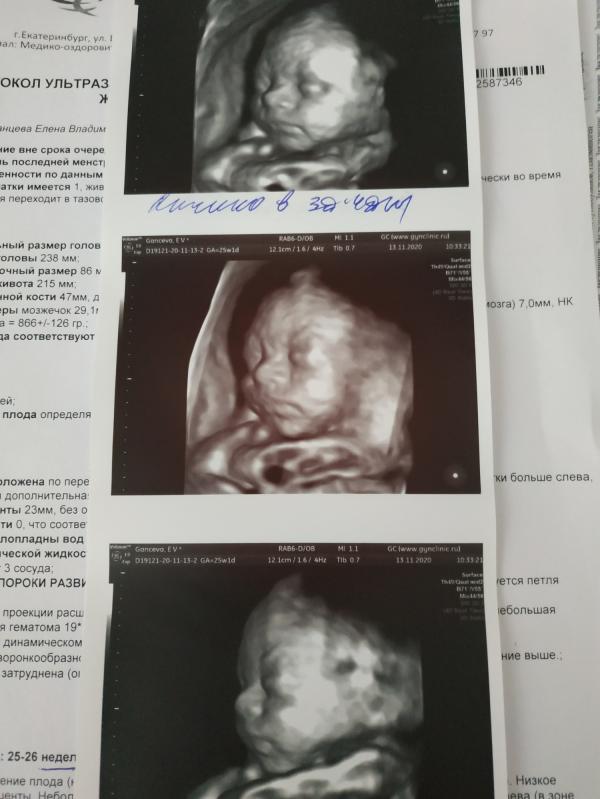

Ну что, сходили мы с мужем сегодня к Ковальчуку на УЗИ. Дело в том, что две недели назад я попала в больницу с сильным кровотечением, однако там мне не смогли установить причину и вообще, сказали, что у меня все хорошо. Продержали несколько дней и отправили домой. И вот эта неопределенность очень пугала меня, я не знала, чего можно дальше ждать, не пропустили ли что-то врачи, нет ли скрытой угрозы для ребенка. Ну и чисто на бытовом уровне, я решила, что надо лежать. Формулировки врачей "угроза п...